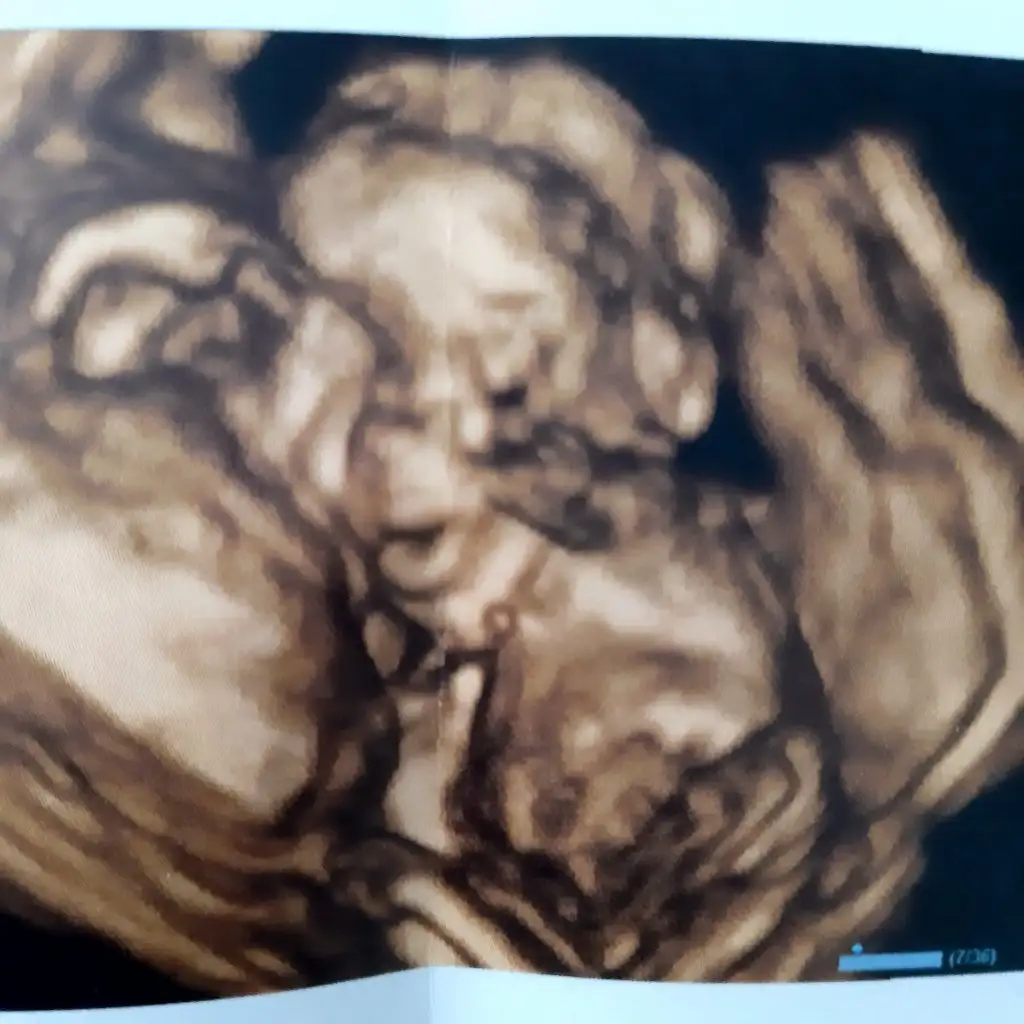

Foti yok muDetaylıdan geliyorum kızlar.

360 gr

23 cm

Minik burunlu

Köfte dudaklı bir kız